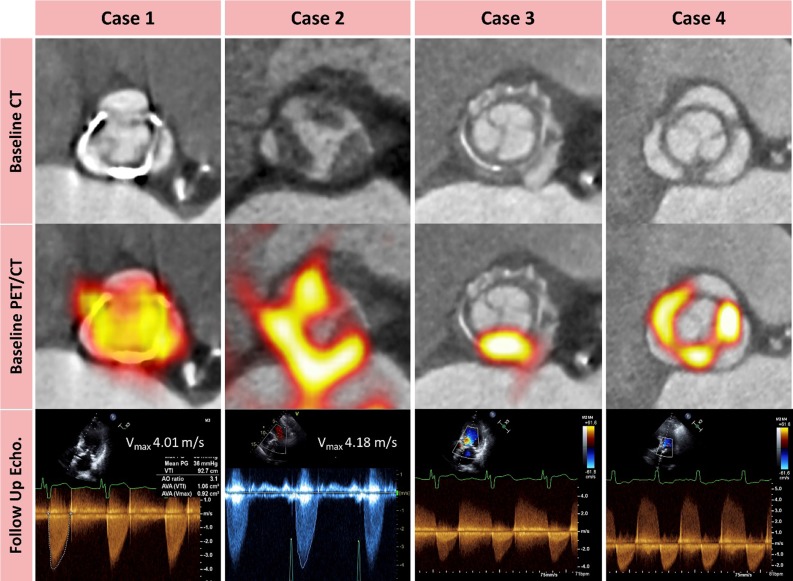

Cartlidge et alref. 9 used 18F-fluoride positron emission tomography (PET) to predict valvular degeneration of bioprosthetic aortic valves. The hypothesis was based on ex vivo experiments in 15 explanted degenerated bioprosthetic valves, which all showed intense 18F-fluoride uptake coregistered to areas of calcification, fibrosis, thrombosis, and disruption of the collagen structure on micro-CT and on histopathology. In the in vivo study, the investigators performed 18F-fluoride PET in 6 patients with aortic bioprosthetic valve dysfunction (cohort 1) and in 71 patients without any known prosthesis dysfunction (cohort 2). Patients were followed up 2 years after PET/CT with echocardiography and clinical assessment. In cohort 1, all patients exhibited increased 18F-fluoride uptake on PET and leaflet abnormalities on CT. Interestingly, in cohort 2, 27 (38%) patients had increased 18F-fluoride uptake with a mean target-to-background (TBR) ratio of 1.55. Patients with increased 18F-fluoride uptake demonstrated a > 10-fold increase in mean gradient over 12 months compared to those without increased uptake (Figure 2). On multivariable analysis, baseline 18F-fluoride uptake was the only independent predictor of deterioration in bioprosthetic function, and all patients with TBR values ≥ 2.5 had evidence of overt bioprosthetic failure within 1 year of imaging. The findings of this study suggest that 18F-fluoride PET may be a powerful tool to detect early bioprosthetic valve degeneration and guide subsequent patient management.